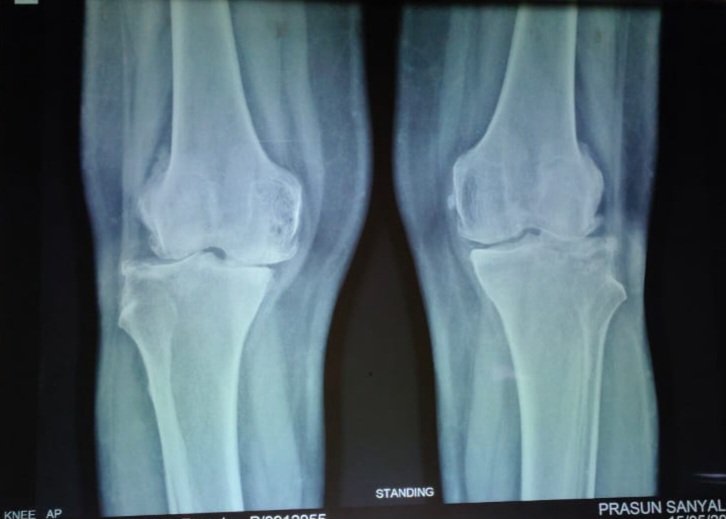

Pre-Op X-Ray